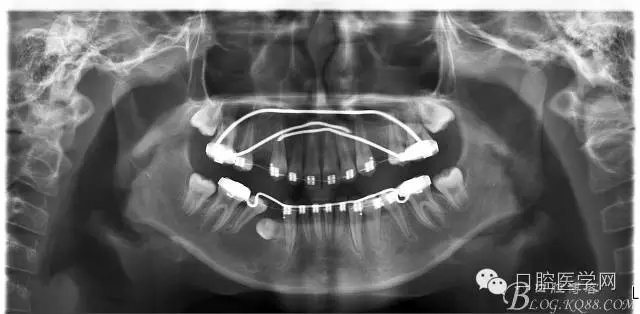

查:右側(cè)第二前磨牙第一乳磨牙恒尖牙頰側(cè)前庭溝隆起,捫有乒乓球感。曲斷及CT示:右側(cè)第二前磨牙第一乳磨牙恒尖牙根尖區(qū)有一囊腫,頰舌側(cè)骨板極薄,牙根無(wú)吸收,第二前磨牙牙根位于囊腫中,第一雙尖牙牙冠遠(yuǎn)中水平向阻生,牙冠位于囊腫中。經(jīng)協(xié)議:手術(shù)摘除創(chuàng)傷大,同意開(kāi)創(chuàng)引流保守治療。

否認(rèn)手術(shù)禁忌癥及過(guò)敏史。消毒,局麻下鋪巾,拔出第一乳磨牙,有囊液溢出,擴(kuò)大開(kāi)放引流孔,取部分囊壁送病理,生理鹽水沖洗,置引流管縫合固定。病理報(bào)告:囊腫。八月后局麻拔除第一雙尖牙刮凈剩余變小的囊壁。

術(shù)后一個(gè)月 三個(gè)月 五個(gè)月 八個(gè)月 拔除第一雙尖牙后 曲斷片: